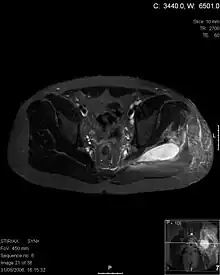

- Axial T1 weighted fat suppressed post IV gadolinium contrast enhanced MRI image showing a mutliloculated bacterial abscess in the left gluteal muscle which grew Staphylococcus aureus (methicillin sensitive) thought to be due to tropical pyomyositis.

- Coronal fat suppressed post contrast image showing a multiloculated bacterial abscess in the left gluteus minimus muscle due to tropical pyomyositis.

- Coronal T2 weighted fat suppressed image showing a multiloculated fluid collection in the left gluteal musculature due to tropical pyomositis in a 12-year-old boy.